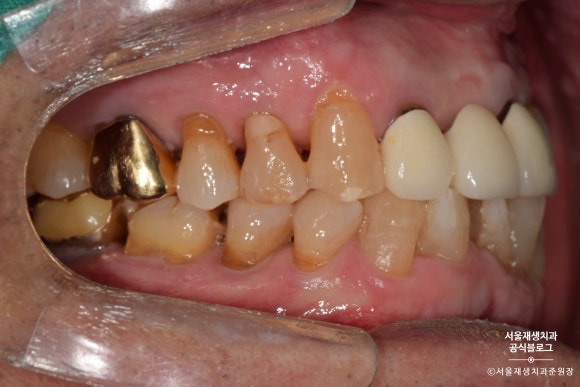

전방치아는 레진으로, 후방치아는 GI로 치료한 사례

여러 치아에 동시에 발생한 치경부마모증을 치료한 사례입니다.

환자분과 거울을 보며 상의한 결과,

잘 보이는 전방 치아는 레진으로,

잘 보이지 않는 후방 치아는 글라스아이오노머로 치료하기로 결정했습니다.

치아의 목 부분, 다시 말해 잇몸과의 경계 부위에

짙은 오렌지색의 띠가 보이시나요?

치아의 겉면은 하얗고 투명한 법랑질인데 반해,

치아의 속살은 노랗고 불투명한 상아질입니다.

법랑질이 모두 마모되어 상아질이 노출되었고,

법랑질에 비해 무른 상아질이 안으로 파고들듯이 마모되고 있는 상태였습니다.

제법 진행이 많이 된 치아를 선별하여

총 4개의 치아를 치료하기로 했습니다.